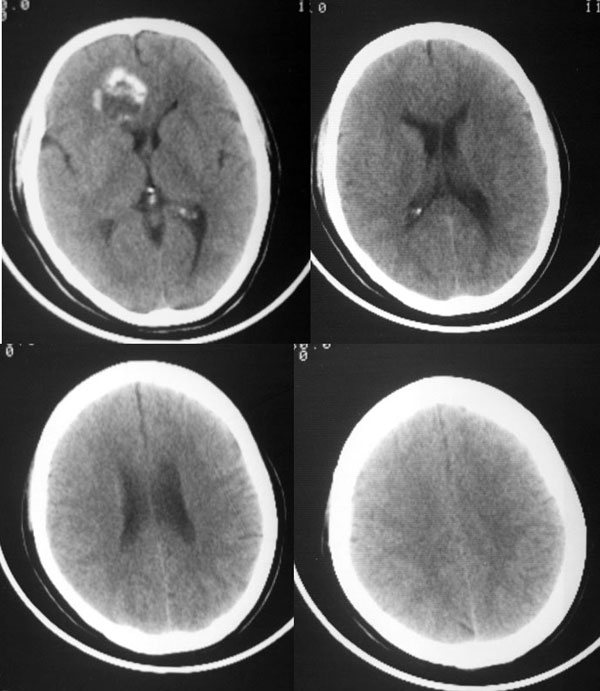

反复头昏1年余...

右额叶内圆形结节状环形钙化块影,周边无水肿.

右前颅窝底圆形钙化影突向额叶内,周围无明显水肿,战位效应轻,考虑脑膜瘤。

平扫前颅底区类圆形骨样高密度影,中心可见低密度影,病变向上生长突入额叶,向下生长突入筛窦,说明病灶来源于额骨水平部,脑膜瘤只能引起颅底骨质的增厚,突入筛窦的几率不大.所以我认为应该首先考虑前颅底骨软骨瘤可能大.如果病变不是来源于颅底骨质,首先应该考虑颅咽管瘤或脑膜瘤.

右前颅窝底圆形钙化影突向额叶内,周围无明显水肿,占位效应轻,考虑脑膜瘤。

前颅窝底肿块,以钙化为主,周围无明显水肿,占位效应轻。考虑:骨软骨瘤或脑膜瘤。

大家看四张骨窗片:病灶最大截面在筛窦,并以此为中心向上侵入额叶,向两侧侵入双眼眶,双眼眶内侧壁亦见骨质吸收破坏,依此可确立病变位于脑外。在此部位符合上述特点的肿瘤,能想到的有骨软骨瘤或脑膜瘤,从常见病考虑,以脑膜瘤可能性大。